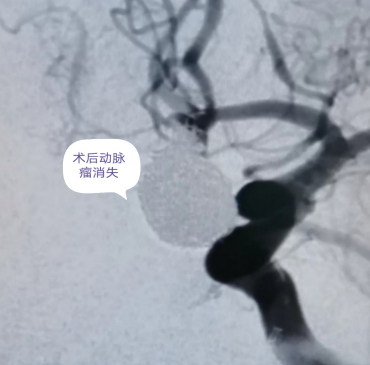

该患者入院时病情危重,脑血管造影提示颅内动脉瘤体积大,约10*12mm大小,属大型动脉瘤,病例类型罕见,且存在随时破裂可能,危及患者生命。传统手术创伤大,风险高,术中破裂概率大,神经外科团队反复研讨病情,结合影像学检查结果,制定了“双微导管技术栓塞动脉瘤”个体化方案。

手术全程在复合手术室下进行,在科主任王伟志的带领下,云亚滨主任医师、荆泽林主治医师、介入导管室及麻醉科成员默契配合,凭借丰富的临床经验避开重要血管与神经,将栓塞材料精准送入动脉瘤腔内,逐步填充、阻断血流,成功实现动脉瘤理想栓塞。历时数小时,手术顺利完成,术后患者生命体征平稳,神情、语利,四肢活动良好,无任何并发症,顺利出院。